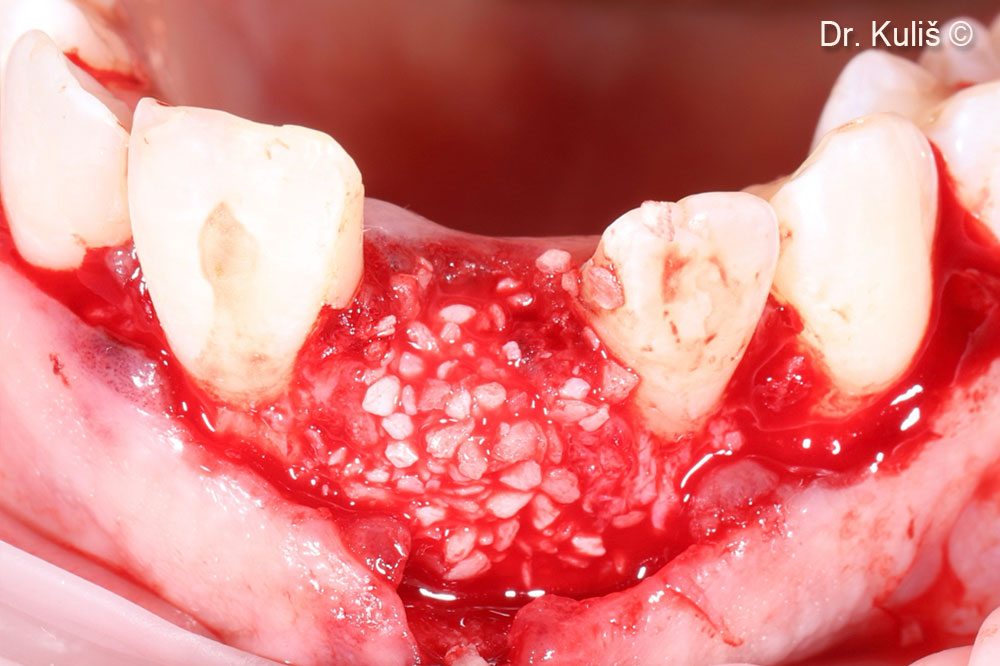

Khuyết tật xương má sau khi nhổ răng và loại bỏ mô hạt

Tăng cường xương bằng mp3®